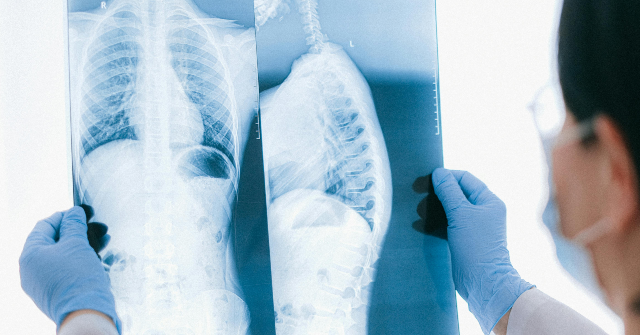

“He suffered three burst fractures of his cervical spine,” said BeDell. “He had an incomplete quadriplegia.”